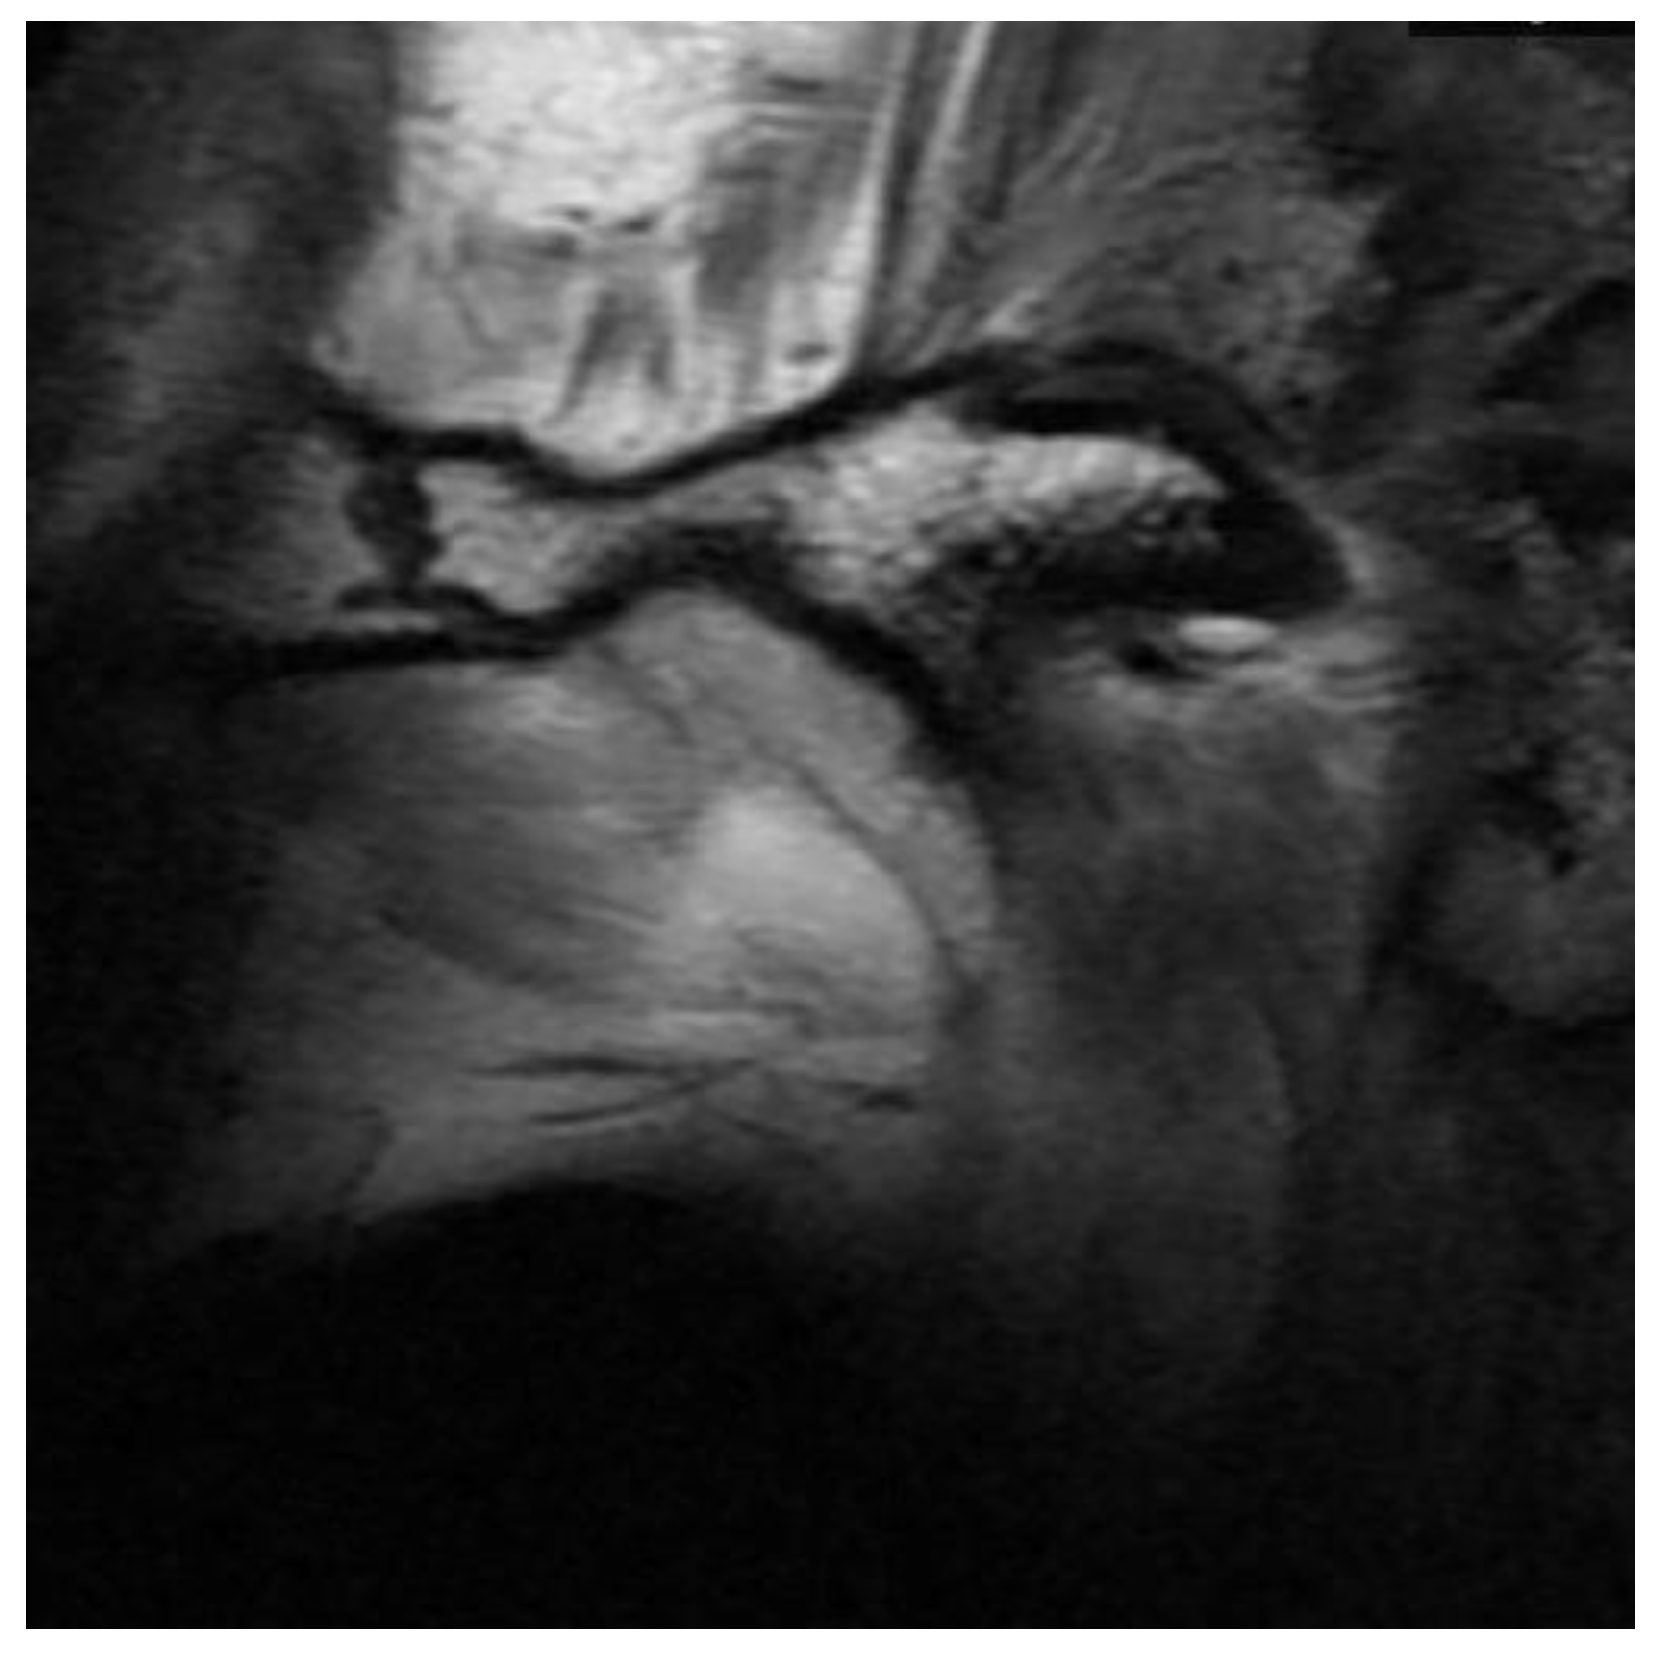

3.2. Definition of Disc Classification